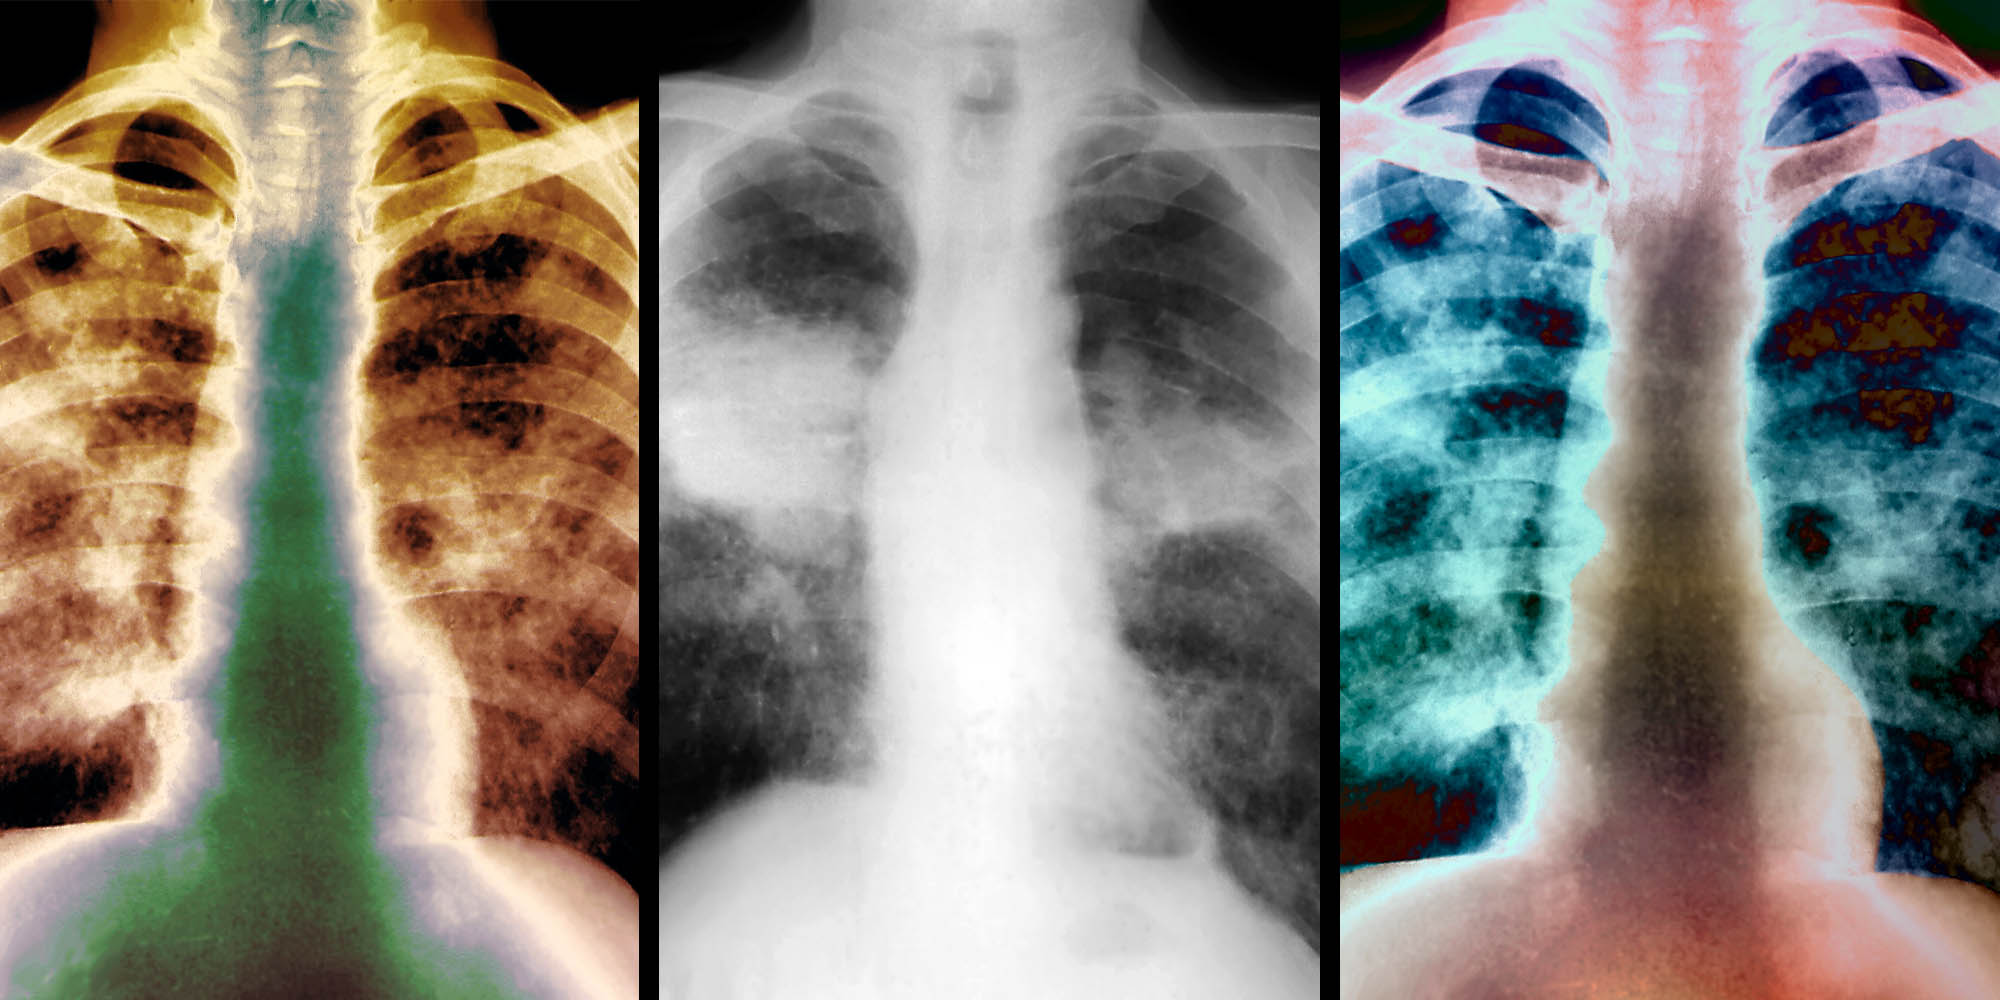

X-rays of the lungs of patients with silicosis, a type of pneumoconiosis. (Photos: Zephyr / Science Photo Library)